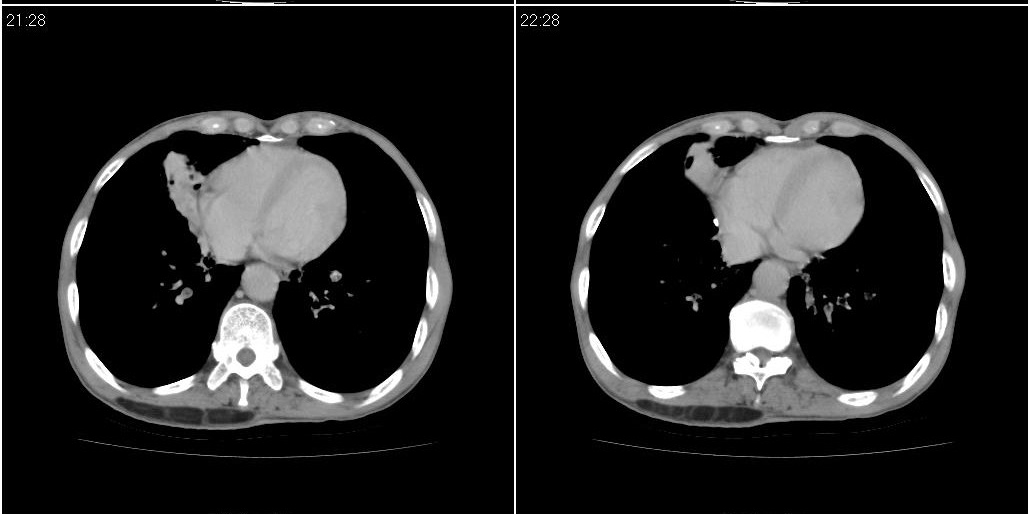

标题: CT25416:男性,70岁。胸片发现右下肺斑片状阴影 [打印本页]

标题: CT25416:男性,70岁。胸片发现右下肺斑片状阴影

以下是ct检查的情况:

考虑右肺下叶炎症可能性大?未除占位,建议增强。右下肺肺不张

右下胸壁皮下气肿。

炎症?占位建议纤支镜或增强检查

右下肺阻塞性肺炎!建议纤支镜!